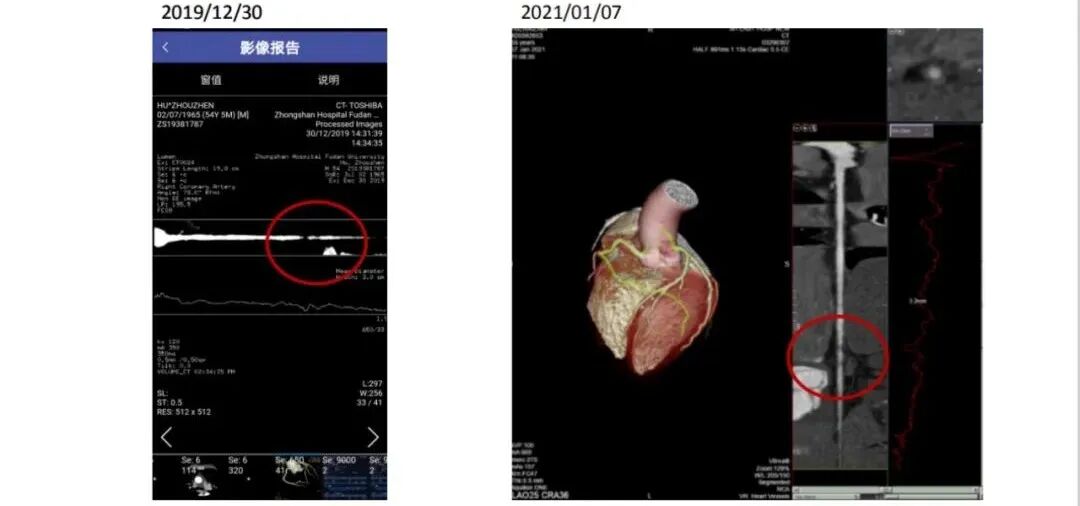

2019年12月,胡先生感到心前区疼痛及压迫感,医院检查之后提示冠状动脉三支病变:左前降支及左旋支狭窄<25%、右冠近段轻度狭窄<25%,右冠远段狭窄>50%近闭塞。

三个月后,等待胡先生的心脏大考即将迎来第一次的康复成绩单,而结果比预想的还要喜人!冠状动脉CTA显示,其右冠状动脉斑块管腔狭窄程度明显变小。也就是说H先生的斑块不仅稳定住了,而且实现了斑块逆转。